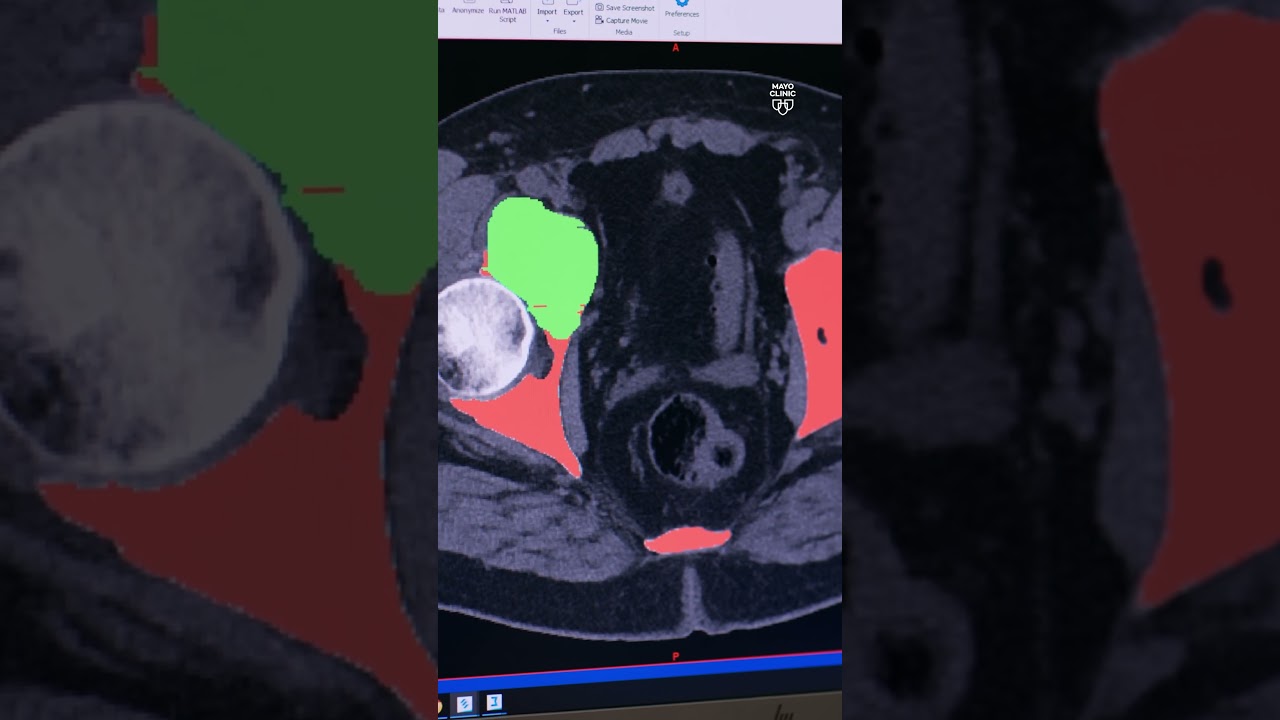

Colon cancer is on the rise. AI is helping to detect it early. [Ad Content from Mayo Clinic]